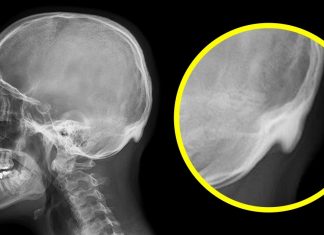

მეცნიერებმა დაადგინეს, რომ სმარტფონებმა უკვე იქონია გავლენა ჩვენი თავის ქალის ფორმაზე

ამერიკელი მეცნიერების მტკიცებით, თანამედროვე ადამიანი დღის განმავლობაში სმარტფონის ეკრანის წინ დაახლოებით 145 წუთს ატარებს, საკუთარ ტელეფონს კი დღე-ღამეში საშუალოდ 3 000-ჯერ ეხება. ამ სტატისტიკის ავტორების ავსტალიელმა კოლეგემა გადაწყვიტეს, ძირფესვიანად შეესწავლათ ამ არც თუ ისე...